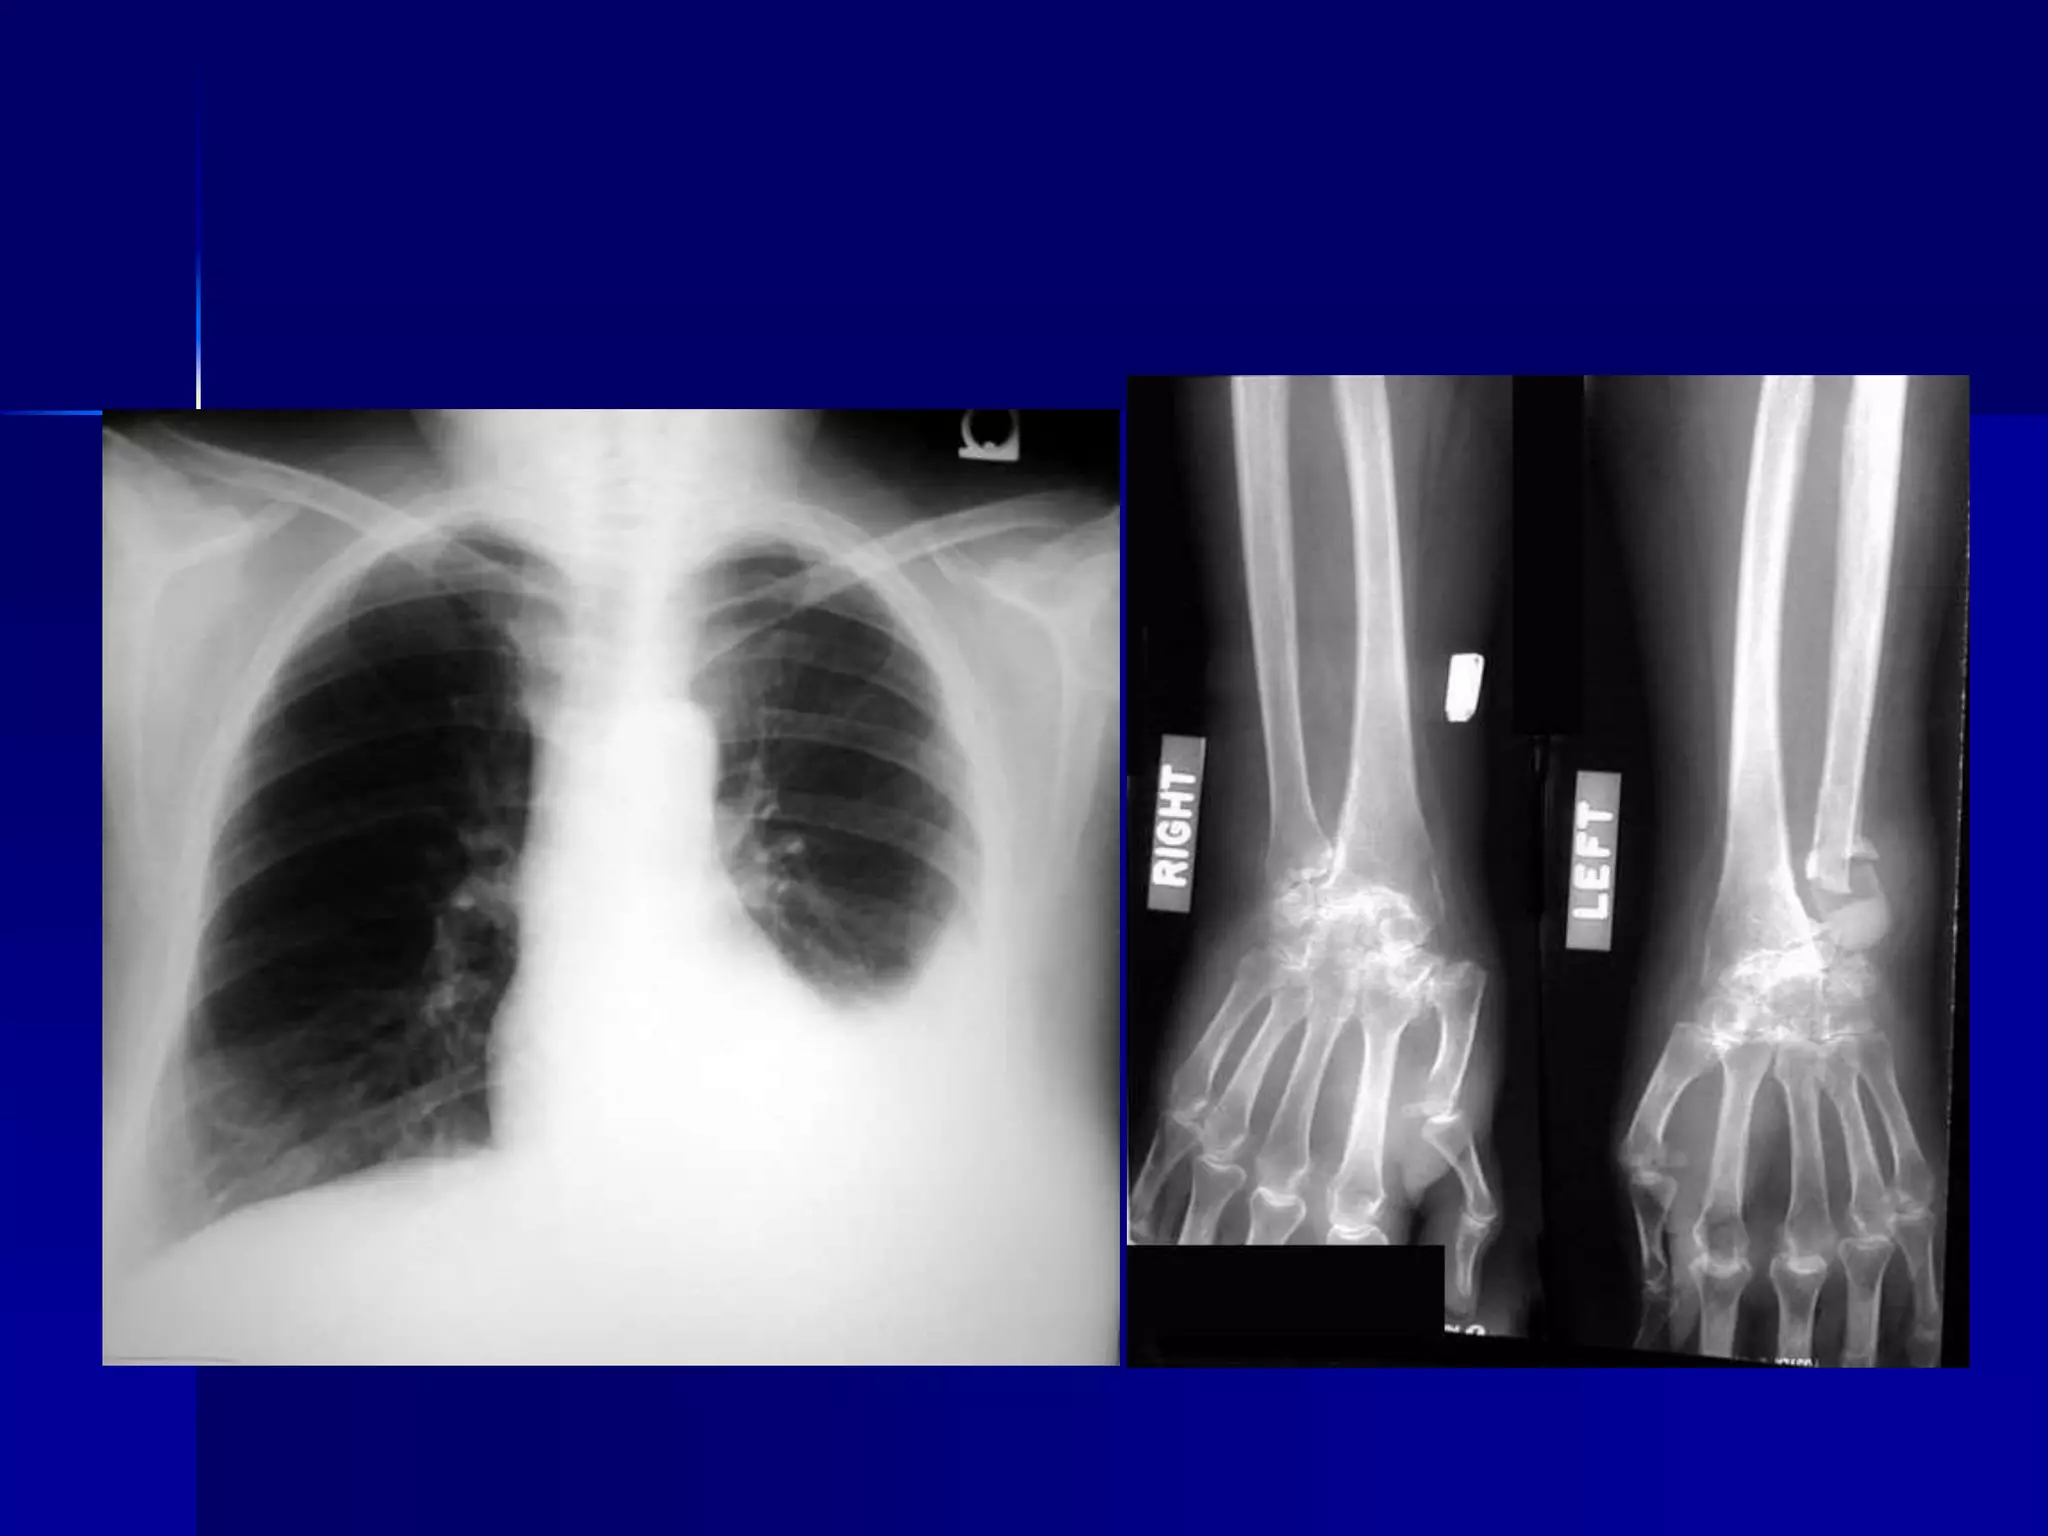

 Pleural Effusion

 Rheumatoid Arthritis

 Chest lateral and hand x-rays.

 Pleural Effusion  Rheumatoid Arthritis  Chest lateral and hand x-rays. 